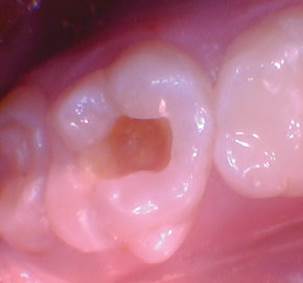

Caso 1

Un paciente de 8 años presentó descomposición de OD en un primer molar primario con síntomas de pulpitis reversible. El diente fue el tratamiento planificado para una restauración de OD con Activa Bioactive Restorative (Pulpdent). Tras la excavación por descomposición, se produjo una exposición pulpar que requirió una pulpotomía terapéutica. Debido a la edad del paciente, me sentí cómodo con una pulpotomía terapéutica con Biodentine (Septodont) seguida de una restauración estética. Si el paciente hubiera tenido entre cuatro y cinco años, me habría restaurado con una corona de acero inoxidable debido a su historial comprobado de longevidad.

Figura 1 Vista preoperatoria del primer molar primario superior. |